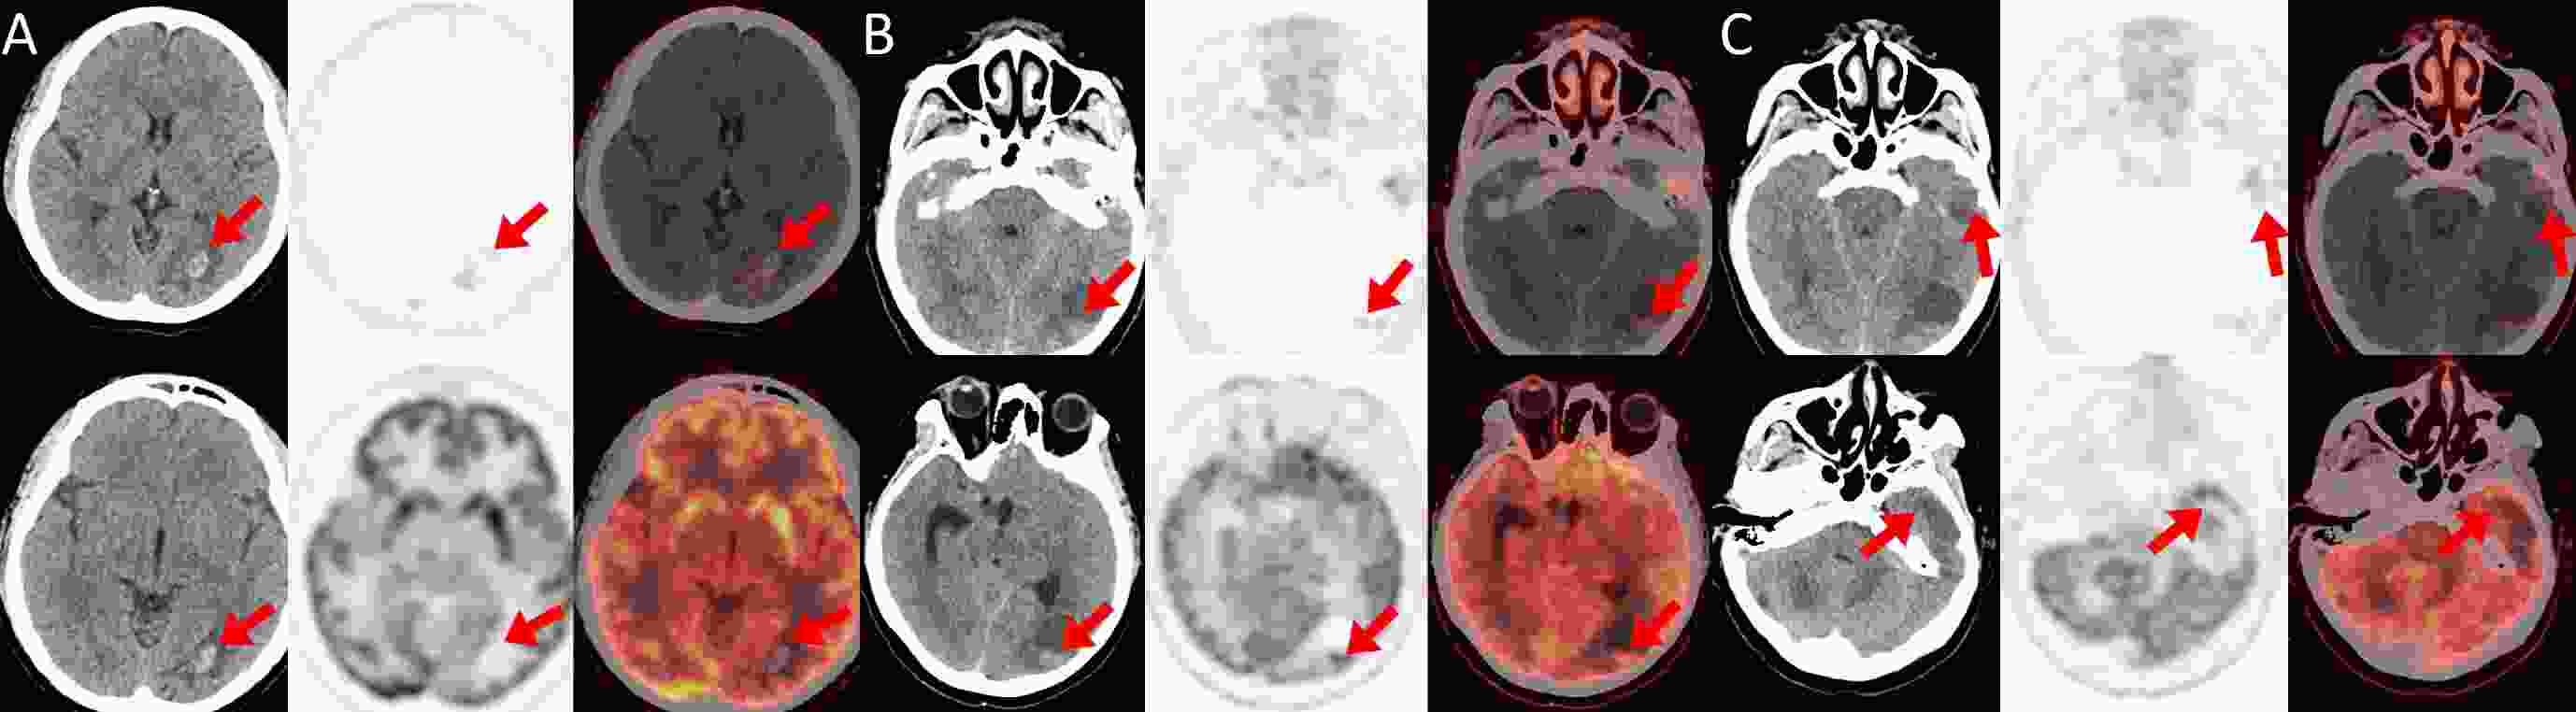

ObjectiveThis study aimed to evaluate the clinical utility of [68Ga]Ga-RM2 positron emission tomography/computed tomography (PET/CT), in comparison with 18F-fluorodeoxyglucose ([18F]FDG) PET/CT, for staging and prognosis in patients with estrogen receptor-positive (ER+) breast cancer. MethodsThis prospective study enrolled nine female patients with breast cancer (mean age 45.5±11.5 years). Eight patients were confirmed to have ER+ disease. All participant underwent both [68Ga]Ga-RM2 PET/CT and [18F]FDG PET/CT scans within a one-week interval. The maximum standardized uptake values (SUVmax) was measured for primary tumors, lymph nodes, and metastatic lesions. The physiological distribution of [68Ga]Ga-RM2 was also evaluated. ResultsNo adverse events were observed. Metastatic were identified in lymph nodes (n=29 lesions), bone (n=19), liver (n=7), brain (n=3), and multiple other sites. [68Ga]Ga-RM2 demonstrated a significantly higher median SUVmax than [18F]FDG across all lesions [7.5 (interquartile range, IQR, 3.4−14.0) vs. 4.0 (IQR, 2.3−6.1); P<0.001]. Similarly, the tumor-to-background ratio (TBR) was significantly superior with [68Ga]Ga-RM2 for all type of lesions: primary tumors [12.3 (IQR, 10.4−18.3) vs. 7.0 (IQR, 6.0−10.0); P<0.001], lymph node metastases [17.8 (IQR, 4.4−39.0) vs. 4.7 (IQR, 2.7−10.2); P<0.001], hepatic metastases [5.4 (IQR, 3.7−8.3) vs. 1.0 (IQR, 0.9−1.5); P<0.001], and osseous metastases [13.9 (IQR, 7.3−18.0) vs. 4.3 (IQR, 1.6−5.9); P<0.001]. Physiological uptake of [68Ga]Ga-RM2 was the highest in the pancreas (SUVmax, 77.82±22.64), with moderate uptake in the kidneys (2.82±0.62), heart (1.83±0.29), and liver (1.33±0.41). Conclusions[68Ga]Ga-RM2 PET/CT demonstrates superior uptake metrics for the detection of metastatic lesions, particularly in the brain and breast, suggesting its potential as a valuable complementary imaging modality to [18F]FDG PET/CT. These promising foundings warrant further validation in larger cohorts to confirm their clinical impact and to standardize imaging protocols.